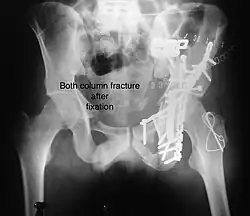

Combined both column fractures These are the most complex injuries. Here the weight bearing roof or dome of the acetabulum is a floating piece. This adds to complexity of management.

All three x-ray views plus CT scan is a must for diagnosis and management of this complex injury.

Treatment

Like any other acetabular fracture, if the femoral head is dislocated out of the socket, early reduction into socket is a priority. However, in this injury, non-operative treatment rarely gives satisfactory results. Surgical management is ideal. The choice of approach rests with the surgeon, but going from front, or anterior approach is must. The posterior injury may be tacked with anterior approach by experienced surgeon. If the patient is unfit to undergo major surgery due to any reason, longitudinal traction to achieve secondary congruence of hip may help to restore hip function, though partially.